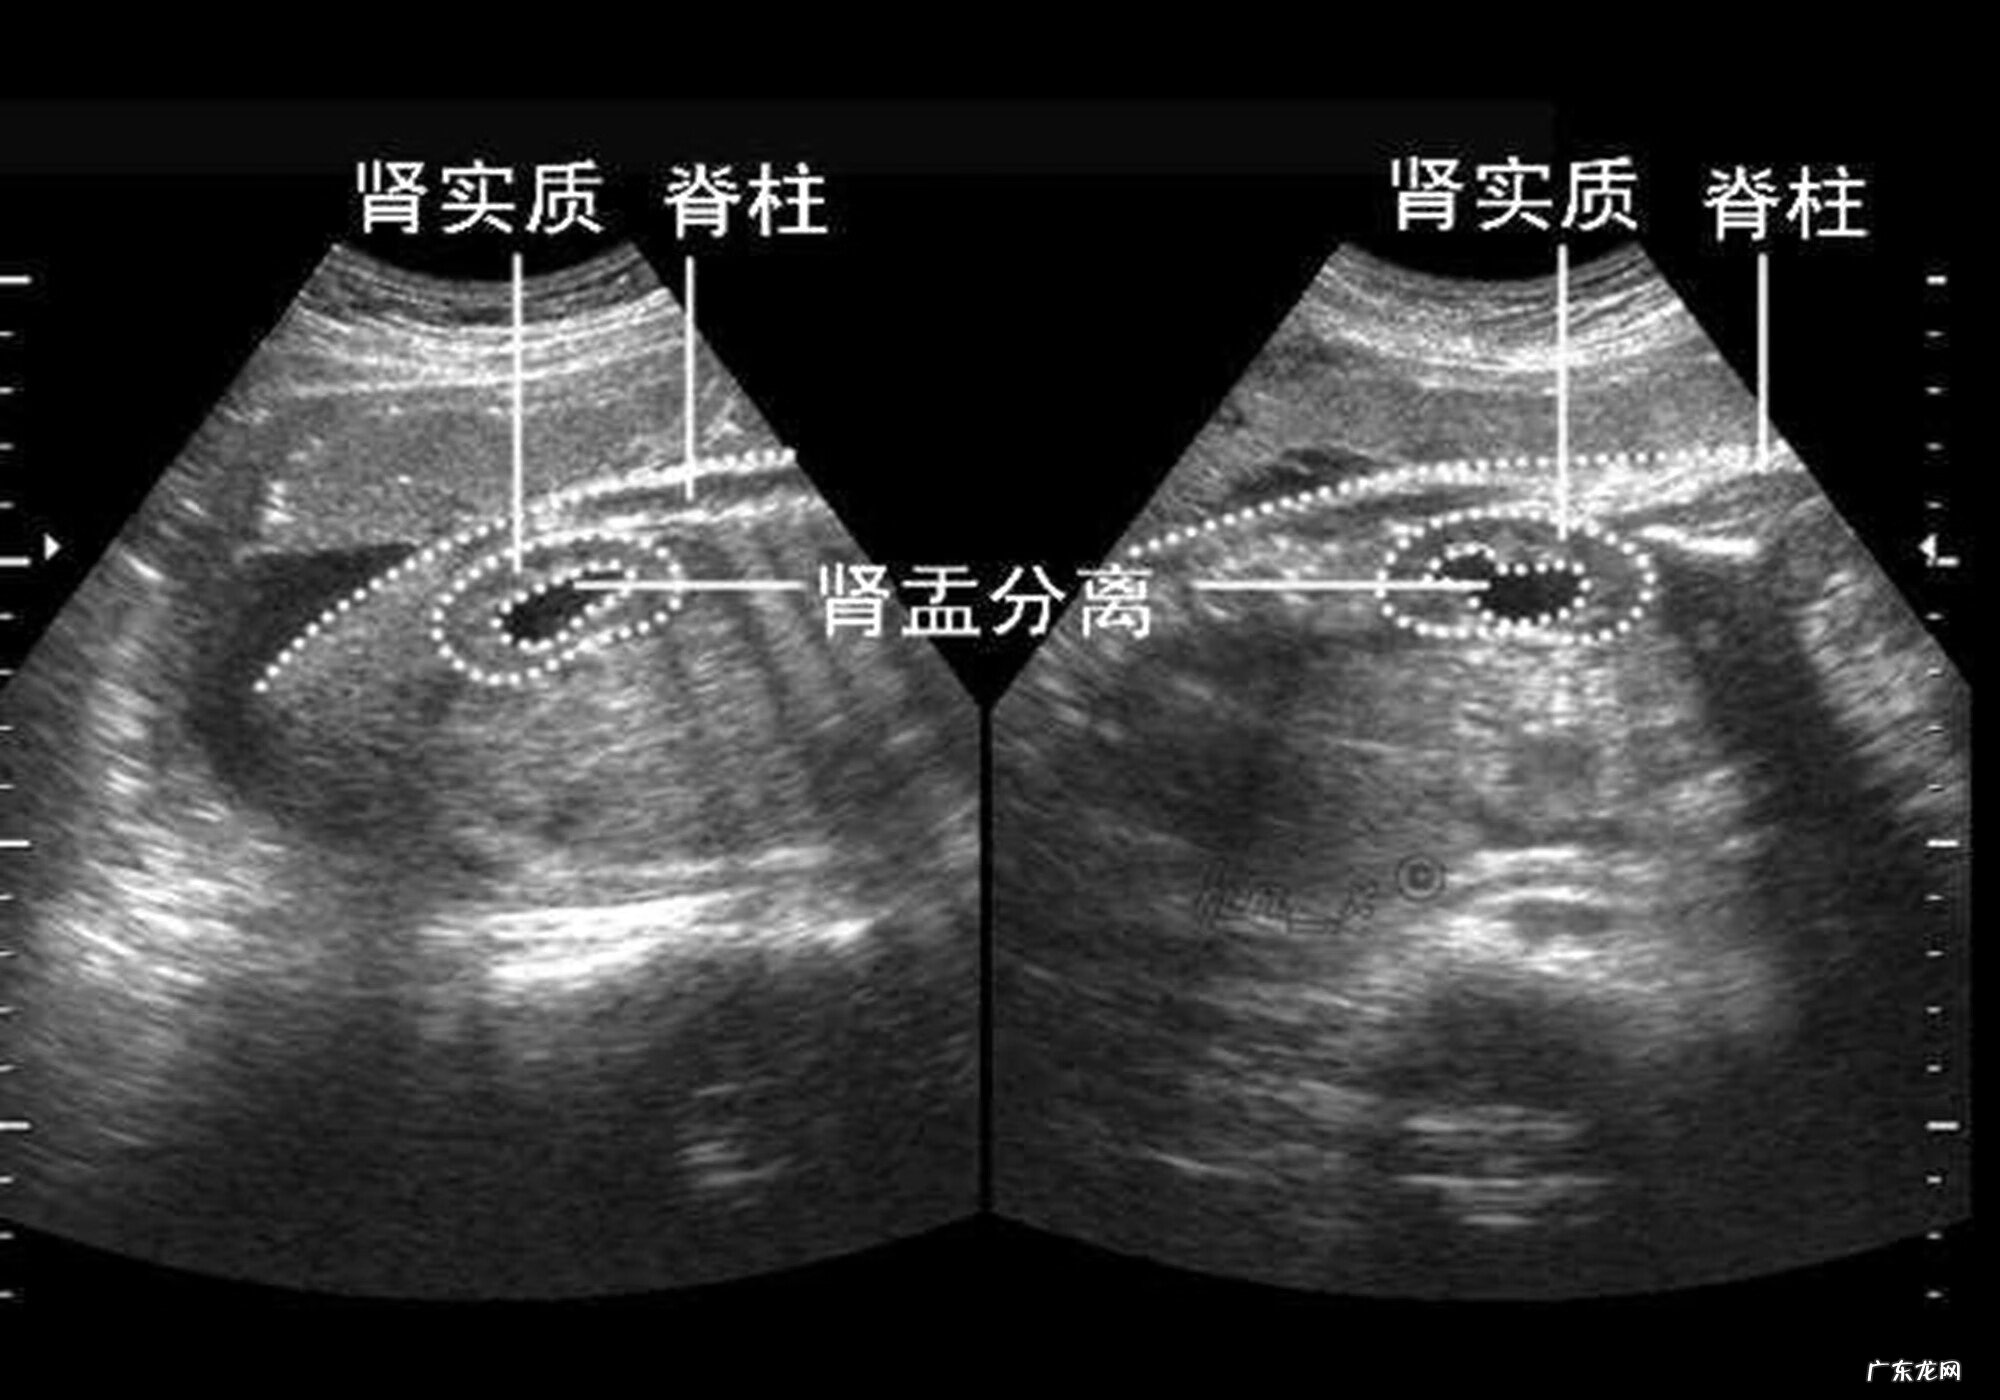

B超单上的“肾盂分离”是啥意思?和性别有关系吗?看完就明白了在这先给大家解释一下,什么叫做“肾盂分离”,肾盂就是肾与尿道连接的那块地儿,它们若没有完全连接在一起,那就叫分离 。

如果肾脏里无积水,那么就不会出现肾盂分离现象,反之,肾脏里要是有积水,就会出现肾盂分离 。正常情况下,9成以上的肾盂分离都是无害的,胎儿分离距离一般在10mm左右(新生儿16mm左右),父母不用为此担心 。

由于生理构造上的原因,男性胎儿经常出现尿滞留现象,因此,他们出现肾盂分离的概率远超女孩,老人将其视为“男娃特征”也在情理之中,从概率学来讲,这不失为一种好办法 。